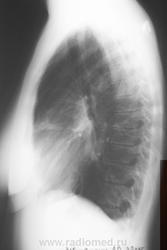

Осумкованный плеврит? в заднем отделе левого синуса.Так ли это?

Собираюсь на консультацию к кардиологу и сегодня сделала рентген в 2 проекциях. И Врач-ренгинолог меня просто ошарашил дословно: Осумкованный плеврит? в заднем отделе левого синуса.

Однозначно, что именно "осумкованного плеврита", в данном случае нет. Однако архивчик есть, да и верхушечки внимания требуют.

Вероятно левосторонняя пневмония в 3-м сегменте.

Здрасти . У вас по снимкам легочный рисунок резко усилен с обоих сторон , справа корень расширен и деформирован .Слева в синусе похоже небольшое количество жидкости ,но насчет осумкованности я сильно сомневаюсь . Вы анализы сдавали ? СОЭ, лейкоциты ..... Верхушки чистые , но вот справа корень и легочный рисунок мне не нравтся , да и что может вызвать выпот в плевральную полость . Было бы хорошо если бы вы сделали манту